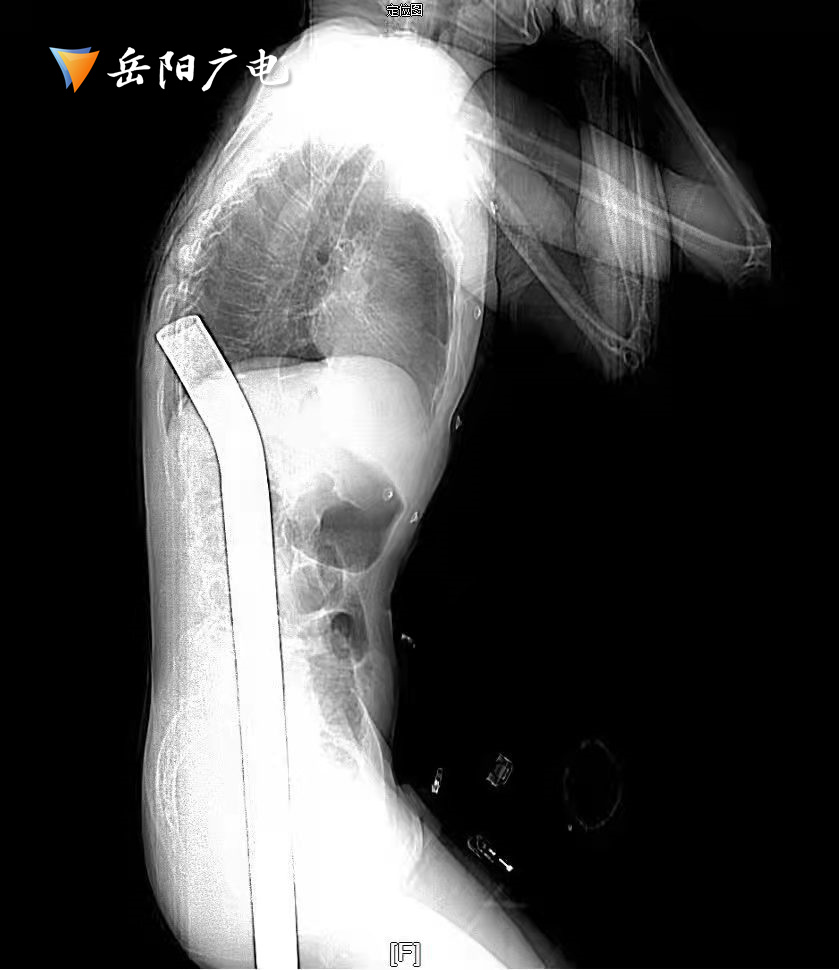

几天前,岳阳县村民刘师傅整理屋顶时,不慎从高空坠落,被1米多长的钢筋贯穿胸腹部。

(影像学照片)